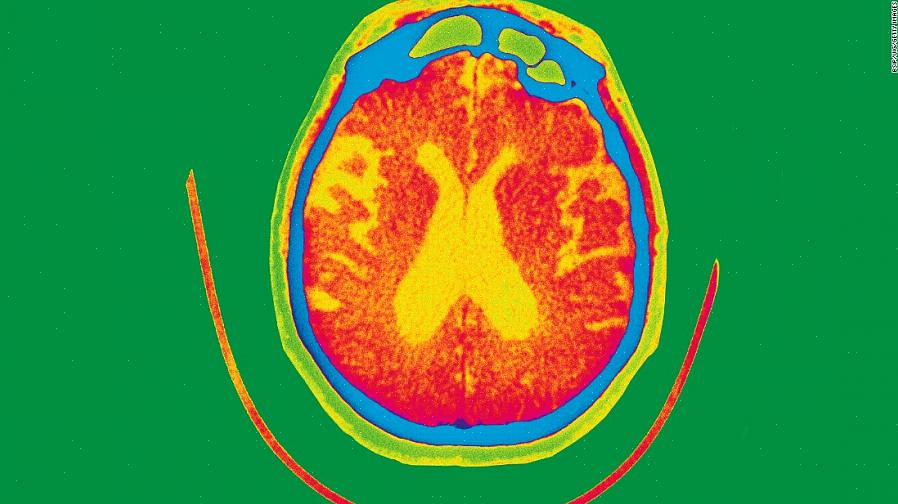

המוח עם דמנציה של אלצהיימר

כאשר מישהו מושפע ממחלת אלצהיימר, מתרחש ניוון רציני של המוח, במיוחד בהיפוקמפוס, הקורטקס האנטורינאלי, הניאוקורטקס (במיוחד קליפת האסוציאציה באונה הקדמית והרקתית), הגרעין הבסיסי, הלוקוס קוירולאוס, ו גרעיני הרפה.

אבל מה זה כל זה? אלו אזורים שונים במוח, שמוסברים בצורה הפשוטה ביותר, מעורבים בתהליך הלמידה, הזיכרון והויסות הרגשי. כפי שניתן לראות, כל התפקודים הללו מושפעים מאוד בחולים עם אלצהיימר.